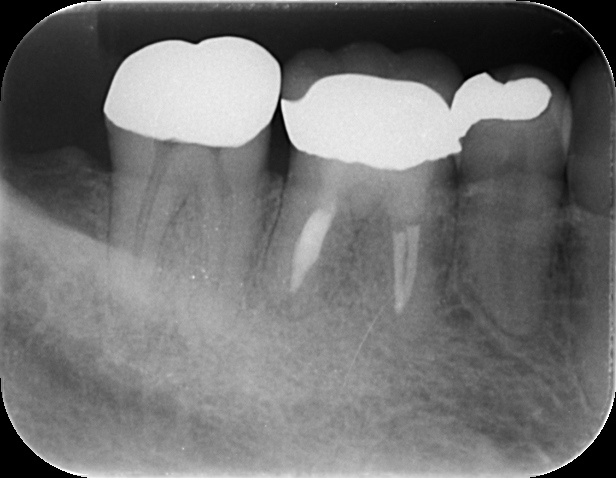

- 10年後の経過:

精密な根管治療を行い、数ヶ月後には骨が再生。10年経った現在も、何でも美味しく噛める状態を維持しています。病変の大きさは、歯の寿命を決める決定打ではありません。